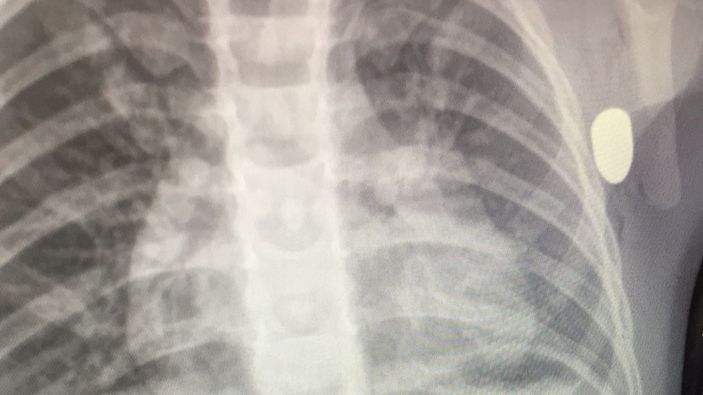

Tedavisi süren Aydemir'in maganda kurşununun hedefi olduğu, yorgun merminin de sol kolunun alt kısmından girip, göğsüne saplandığı tespit edildi.